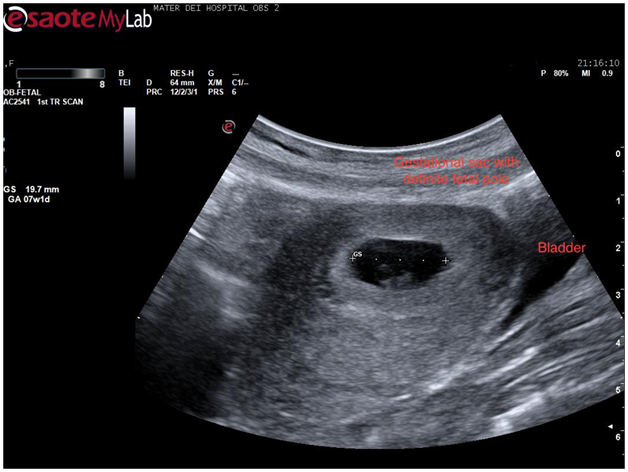

On placing the curvilinear probe on the patient’s abdomen a sagittal view of the uterus was obtained. The bladder was only slightly filled however a good view of the uterus, cervix, and vagina was obtained. Usually, in this view, the endometrial stripe is apparent. In this case, it became apparent that the uterus had a congenital anomaly as 2 horns were clearly visible (Figure 1).

Figure 1 Trans abdominal ultrasound showing a sagittal view of the uterus. Two horns are apparent with a possible gestational sac in the left horn.

A closer look at the hypo echoic mass in the right horn of the uterus revealed what appeared to be a gestational sac measuring almost 20mm. By zooming in onto the sac a definite fetal pole together with a yolk sac came into view. This confirmed the hypo echoic area to be a gestation sac and hence an intrauterine pregnancy (Figure 2). The pregnancy was viable as a fetal heart beat was seen.

Figure 2 Transabdominal scan showing a transverse view of the uterus with a definite gestational sac inside one of the horns.